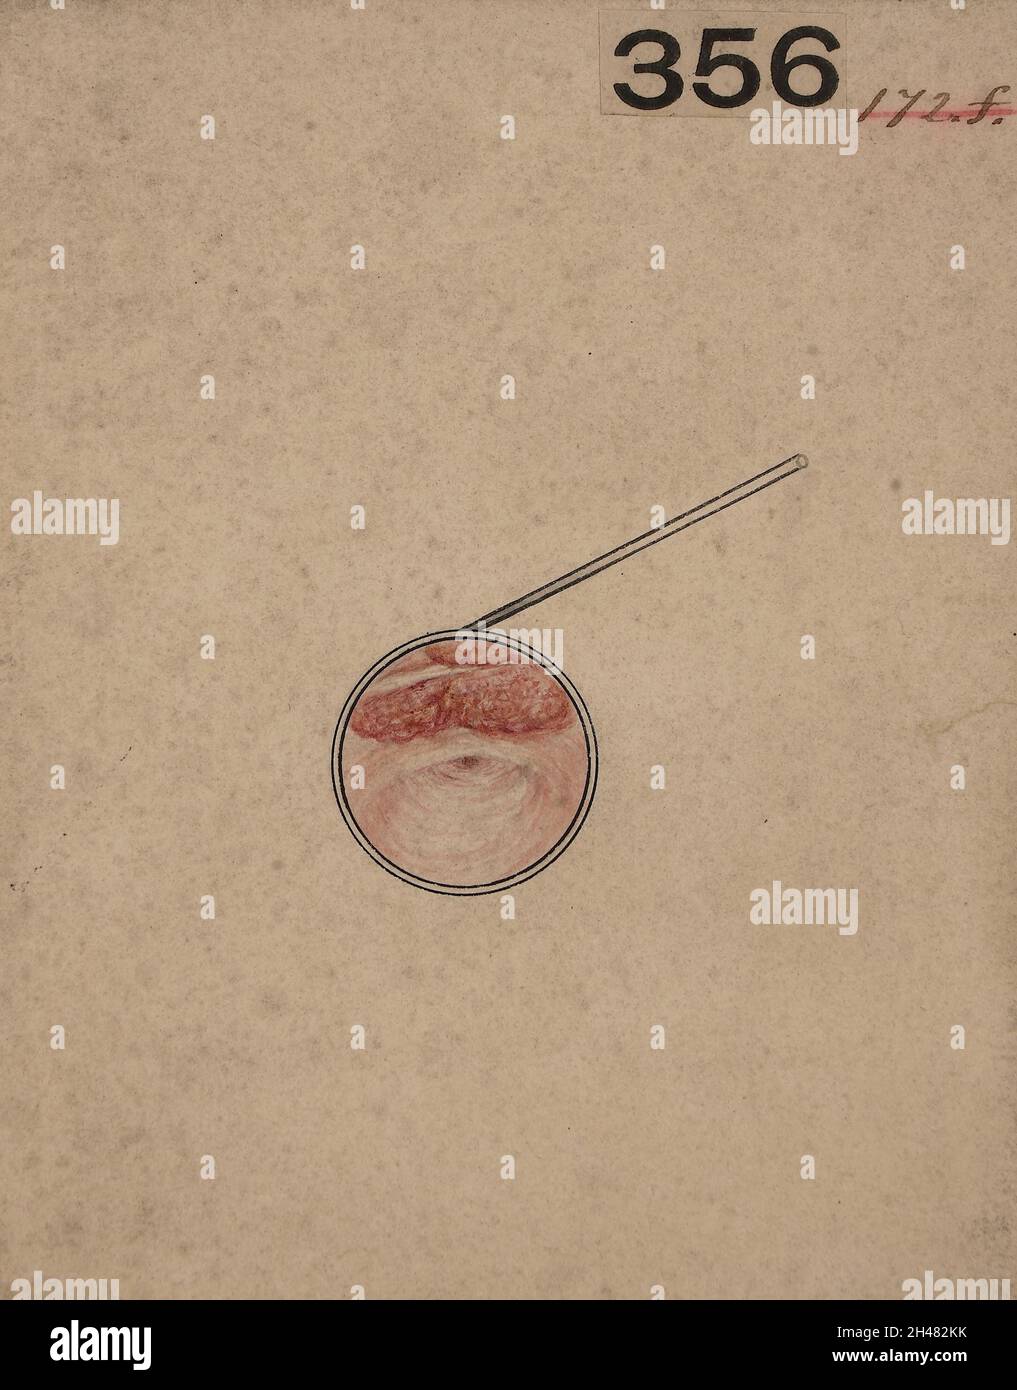

Laryngoscopic view of a constriction of the naso-pharyngeal aperture Stock Photohttps://www.alamy.com/image-license-details/?v=1https://www.alamy.com/laryngoscopic-view-of-a-constriction-of-the-naso-pharyngeal-aperture-image450105927.html

Laryngoscopic view of a constriction of the naso-pharyngeal aperture Stock Photohttps://www.alamy.com/image-license-details/?v=1https://www.alamy.com/laryngoscopic-view-of-a-constriction-of-the-naso-pharyngeal-aperture-image450105927.htmlRM2H482KK–Laryngoscopic view of a constriction of the naso-pharyngeal aperture